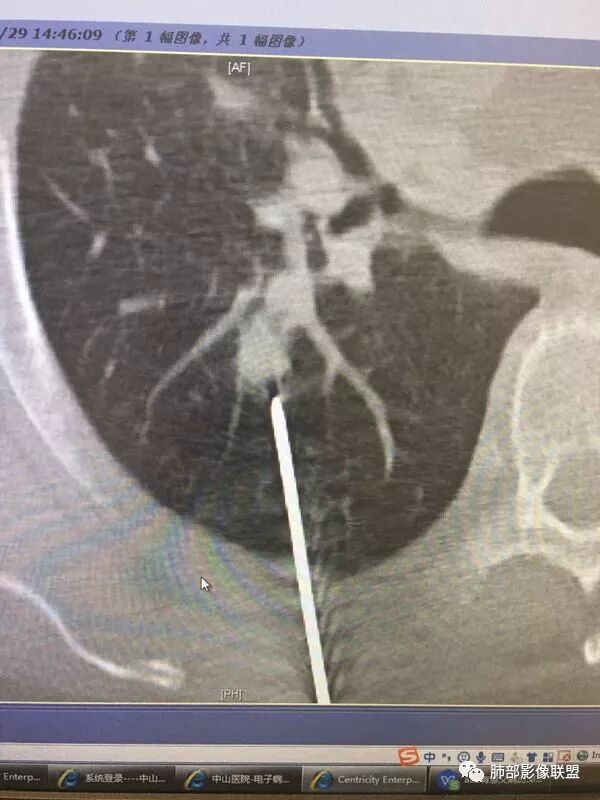

其实这个病人能取到病理也要感谢放射介入组的强大,取到也很不容易了。那么小的结节,取得组织量又少病理科也很给力。